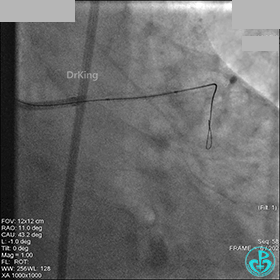

AL 1.0指引导管到位,简单短时尝试导丝不能顺利通过前降支或回旋支病变。改变策略处理右冠脉病变,计划植入2枚支架。AL指引导管到位,Sion blue导丝到达右冠脉远端。导丝通过后1.5mm及2.5mm球囊14~16atm充分扩张中段病变。

右冠脉中段充分扩张后欲植入3.5×38mm支架时,支架难以通过中远段扭曲处,且指引导管、导丝弹出飞扬。反复尝试导丝重新到达右冠脉远端时通过不顺利,局部造影剂滞留,远端血流接近3级。